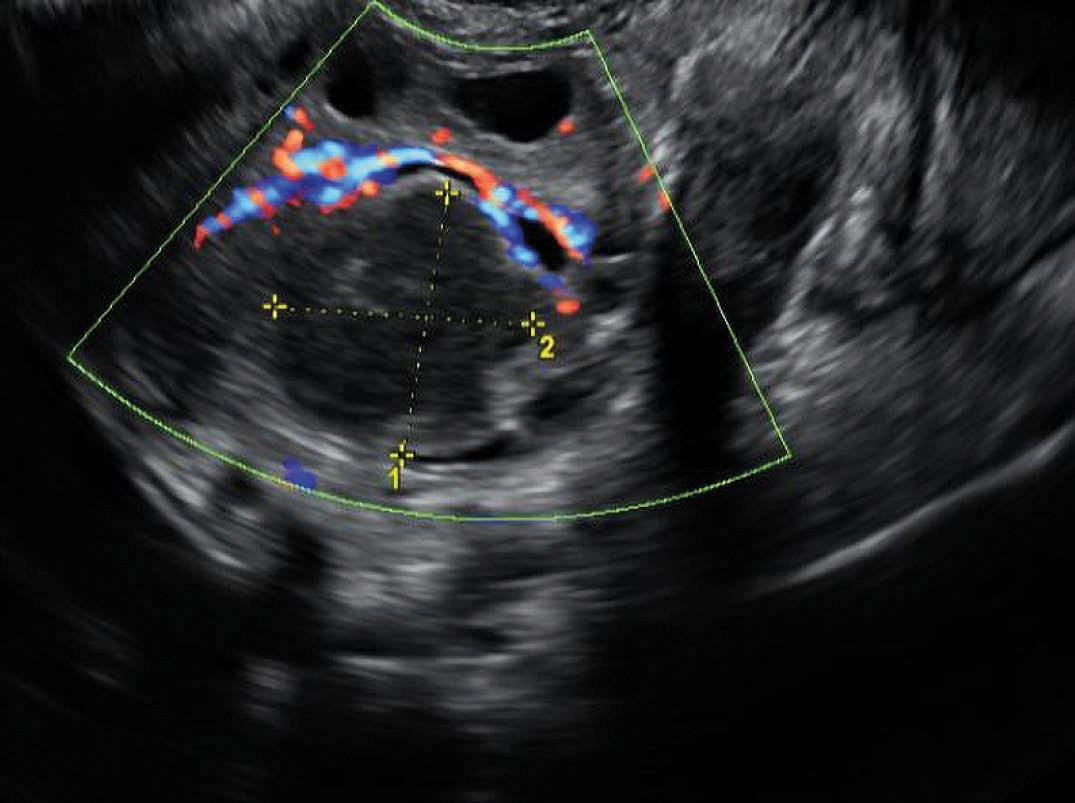

Ved gynekologisk undersøkelse var pasienten påfallende smertepåvirket ved innsetting av vaginalt spekulum. Det var rikelig gulaktig, seigtflytende utflod uten spesiell lukt. Transvaginal ultralydundersøkelse viste bilaterale ekkofattige oppfylninger i ovariene (figur 2). Det ble utført ultralydveiledet transvaginal punksjon med moderat utbytte av puss. Dette ble dyrket med tanke på gonokokker og mykobakterier i tillegg til vanlig aerob og anaerob dyrkning. Prøvematerialet ble sendt på baktuspinne (eSwab). Det ble utført ny mikrobiologisk testing fra cervix- og vaginalsekret med PCR for Chlamydia trachomatis og Neisseria gonorrhoeae. Antibiotika ble i samråd med infeksjonsmedisiner skiftet til ceftriakson og metronidazol. Dette regimet er virksomt mot bukabscess samt gonokokker.